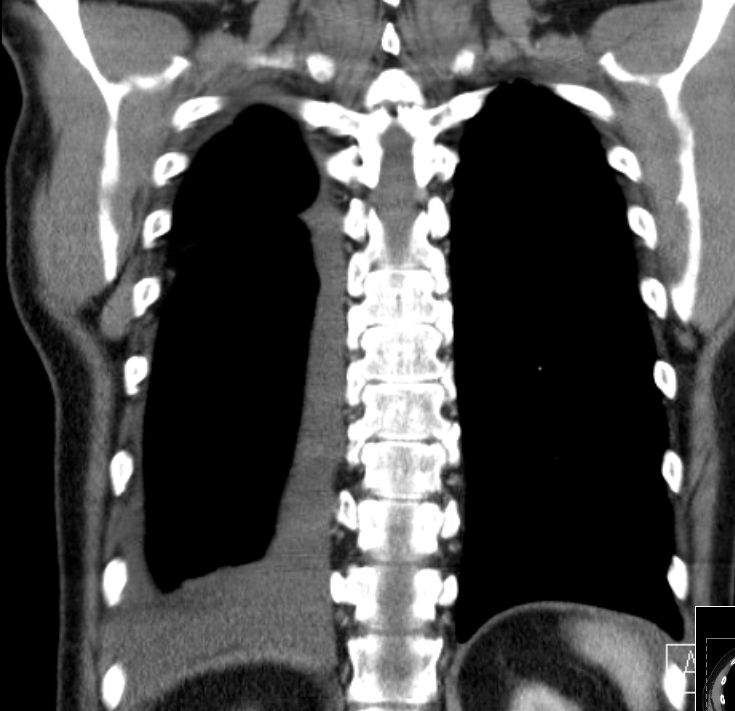

| CT | Tumorausdehnung, Lymphknotenmetastasen (2) | 75-jähriger Mann mit langer Asbest-Exposition. Starke therapieresistente Schmerzen des rechten Thorax.![]() |